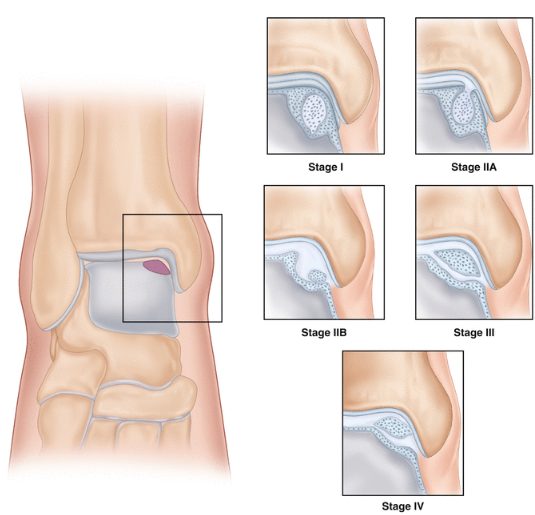

Berndt и Harty (1959) — рентгенологическая

Первая и наиболее известная классификация, предложенная на основании кадаверных экспериментов и рентгенологических данных. Остаётся базовой для первичной оценки:

| Стадия | Описание | Клиническое значение |

|---|---|---|

| I | Компрессия субхондральной кости (bone bruise) | Хороший прогноз при консервативном лечении |

| II | Частично отделённый остеохондральный фрагмент | Может заживать консервативно; при нестабильности — операция |

| III | Полностью отделённый недислоцированный фрагмент | Нестабильный — показана хирургическая фиксация или удаление |

| IV | Смещённый фрагмент (свободное внутрисуставное тело) | Абсолютное показание к операции |

Ограничение: стандартная рентгенография не выявляет до 43% ОХП (Hepple, 1999). Классификация не учитывает состояние хряща и не позволяет дифференцировать острые и хронические повреждения.

Рис. 2. Рентгенологическая классификация остеохондральных повреждений таранной кости по Berndt и Harty (1959)

- Berndt-Harty — для первичной рентгенологической оценки и коммуникации между специалистами